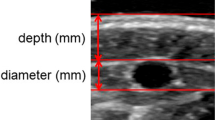

We derived the forearm microvascular bed volumes from the sum of oxygenated hemoglobin/myoglobin (oxyHb/Mb) and deoxygenated Hb/Mb (deoxy Hb/Mb) μM concentrations ([Hb]tot/[Mb]tot) measured using a NIMO-4 continuous-wave photometer (Nirox srl, Brescia, Italy)8. Then, we calculated the blood volume per 100 mL of tissue after accounting for the mean corpuscular hemoglobin concentration, mean corpuscular volume, and hematocrit levels in each participant. Since the Hb in arterioles accounts for only 3% of the NIRS signal, and because these vessels as well as capillaries are poorly distensible9, the changes in [Hb]tot during venous compression represented almost exclusively the changes that occurred in the venules and small veins. Data were acquired at a sampling time of 0.1 s, thus facilitating analysis of rapid changes in the [Hb] levels with a dedicated NIMO software program.

The red blood cell count, cell volumes and the mean corpuscular hemoglobin content were obtained for each participant. To avoid unnecessary insertion of arterial catheters, in healthy participants the arterial blood pressures was recorded non-invasively by a pneumatic cuff, whereas in patients we used data from the invasive devices they had for cardiovascular monitoring. The choice of allowing two different technologies for measuring the arterial pressure was made as, in the range of pressure we studied, the mean arterial pressure was shown to differ little between the invasive and non-invasive approach10. In addition, arterial pressure does not interfere with blood volume changes due to venous occlusions11.

We performed measurements in the dominant forearm and positioned a NIRS probe at the top of the flexor digitorum superficialis (FDS) muscle and verified the correct placement of the probe visually. A pneumatic cuff was placed around the arm 5 cm proximal to the antecubital crease, with its tube connected to an automatic inflation system (model E-20, Hokanson Rapid Cuff Inflator and AG101 Air Source; PMS Instruments Ltd, Maidenhead, UK) capable of reaching a manually predefined pressure in less than 0.5 s. To ensure that there were no differences in hydrostatic pressure due to the position of the forearm during measurement and that no correction factor was needed, we restrained the forearm in a plastic frame at an angle of 135° in relation to the upper arm and placed the NIRS probe at the same level as the right atrium12. The study took place in temperature-controlled rooms, and participants were made to lie down in a comfortable position. To extend the range of values, we experimentally increased the extravascular pressure by graded muscle isometric contractions in healthy participants.

In this study, unlike in previous ones5,6,7, we first inflated the cuff to 50 mmHg for 120 s, according to Halliwill’s technique13, to ensure equilibrium between the cuff pressure (Pcuff) values and intravascular pressure (Pi) and achieve their equivalence14. Then we decreased Pcuff by 5 mmHg down to 0 mmHg, with each step lasting 20 s (10 data points). The five [Hb]tot values preceding each Pcuff drop of 5 mmHg were manually averaged into 1 value from 50 to 0 mmHg, obtaining 10 steady volume values to generate P–V curves. In both methods, it is believed that applying a pressure P with a cuff to the arm generates an extra downstream pressure and blood volume increase that overcomes the baseline venule pressure (P0) (i.e. the mean systemic filling pressure).